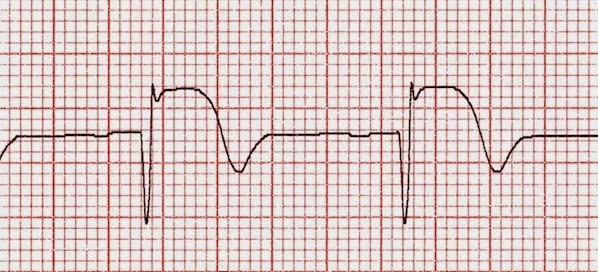

Percepción pronóstica de pacientes y de médicos en insuficiencia cardíaca avanzada

Una estimación precisa del pronóstico permite decidir sobre tratamientos como trasplante cardíaco o implante de dispositivo de asistencia ventricular; sin embargo, las percepciones de pacientes y médicos son discordantes, y ninguna de ellas resulta muy acertada. JACC, 1º de septiembre de 2017